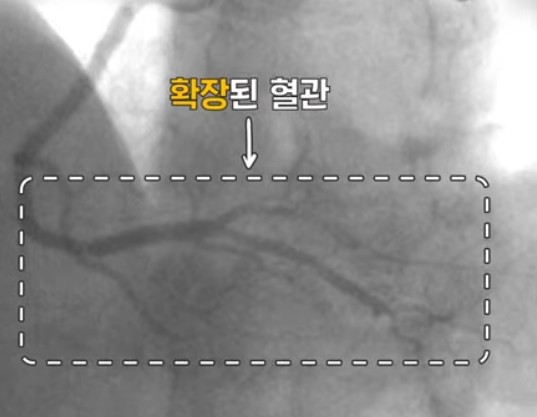

변이형 협심증(variant angina)은 심장에 혈액을 공급해 주는 관상동맥이 수축 즉 경련을 하면서

일시적 혈류 차단에 의해 가슴 통증과 무거운 것에 짓눌리는 압박감 느낌이 나는 증상이 나타는데요.

자극이 없어지면 혈관은 다시 정상을 회복하는데 마치 자다가 근육에 쥐가 났다가 풀리는 증상과 비슷하다고 합니다.

문제는 혈관이 수축(경련)하는 상태가 지속되면 급성 심근 경색증, 부정맥등의 합병증이 생기고 급성 심정사로 이어질 수 있기 때문에 위험요인이 있으시는 분은 정확한 진단과 치료를 받으시고 정기적인 검사를 하는 것이 치료와 예방에 아주 중요합니다.